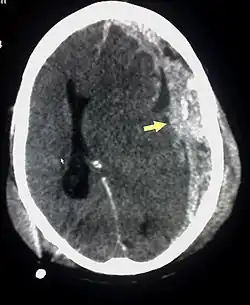

Als Primärdiagnostik erfolgt aufgrund der schnellen Verfügbarkeit häufig eine kranielle CT. Hierbei lassen sich die typischen subduralen Hämatome sowie posttraumatischen Hygrome nachweisen. Zur weiteren Diagnostik und zur Verlaufskontrolle wird eine MRT eingesetzt. Diese kommt bei Verfügbarkeit auch während der initialen Diagnostik zum Einsatz. Zur Diagnostik der retinalen Blutungen erfolgt eine Fundoskopie.[5]